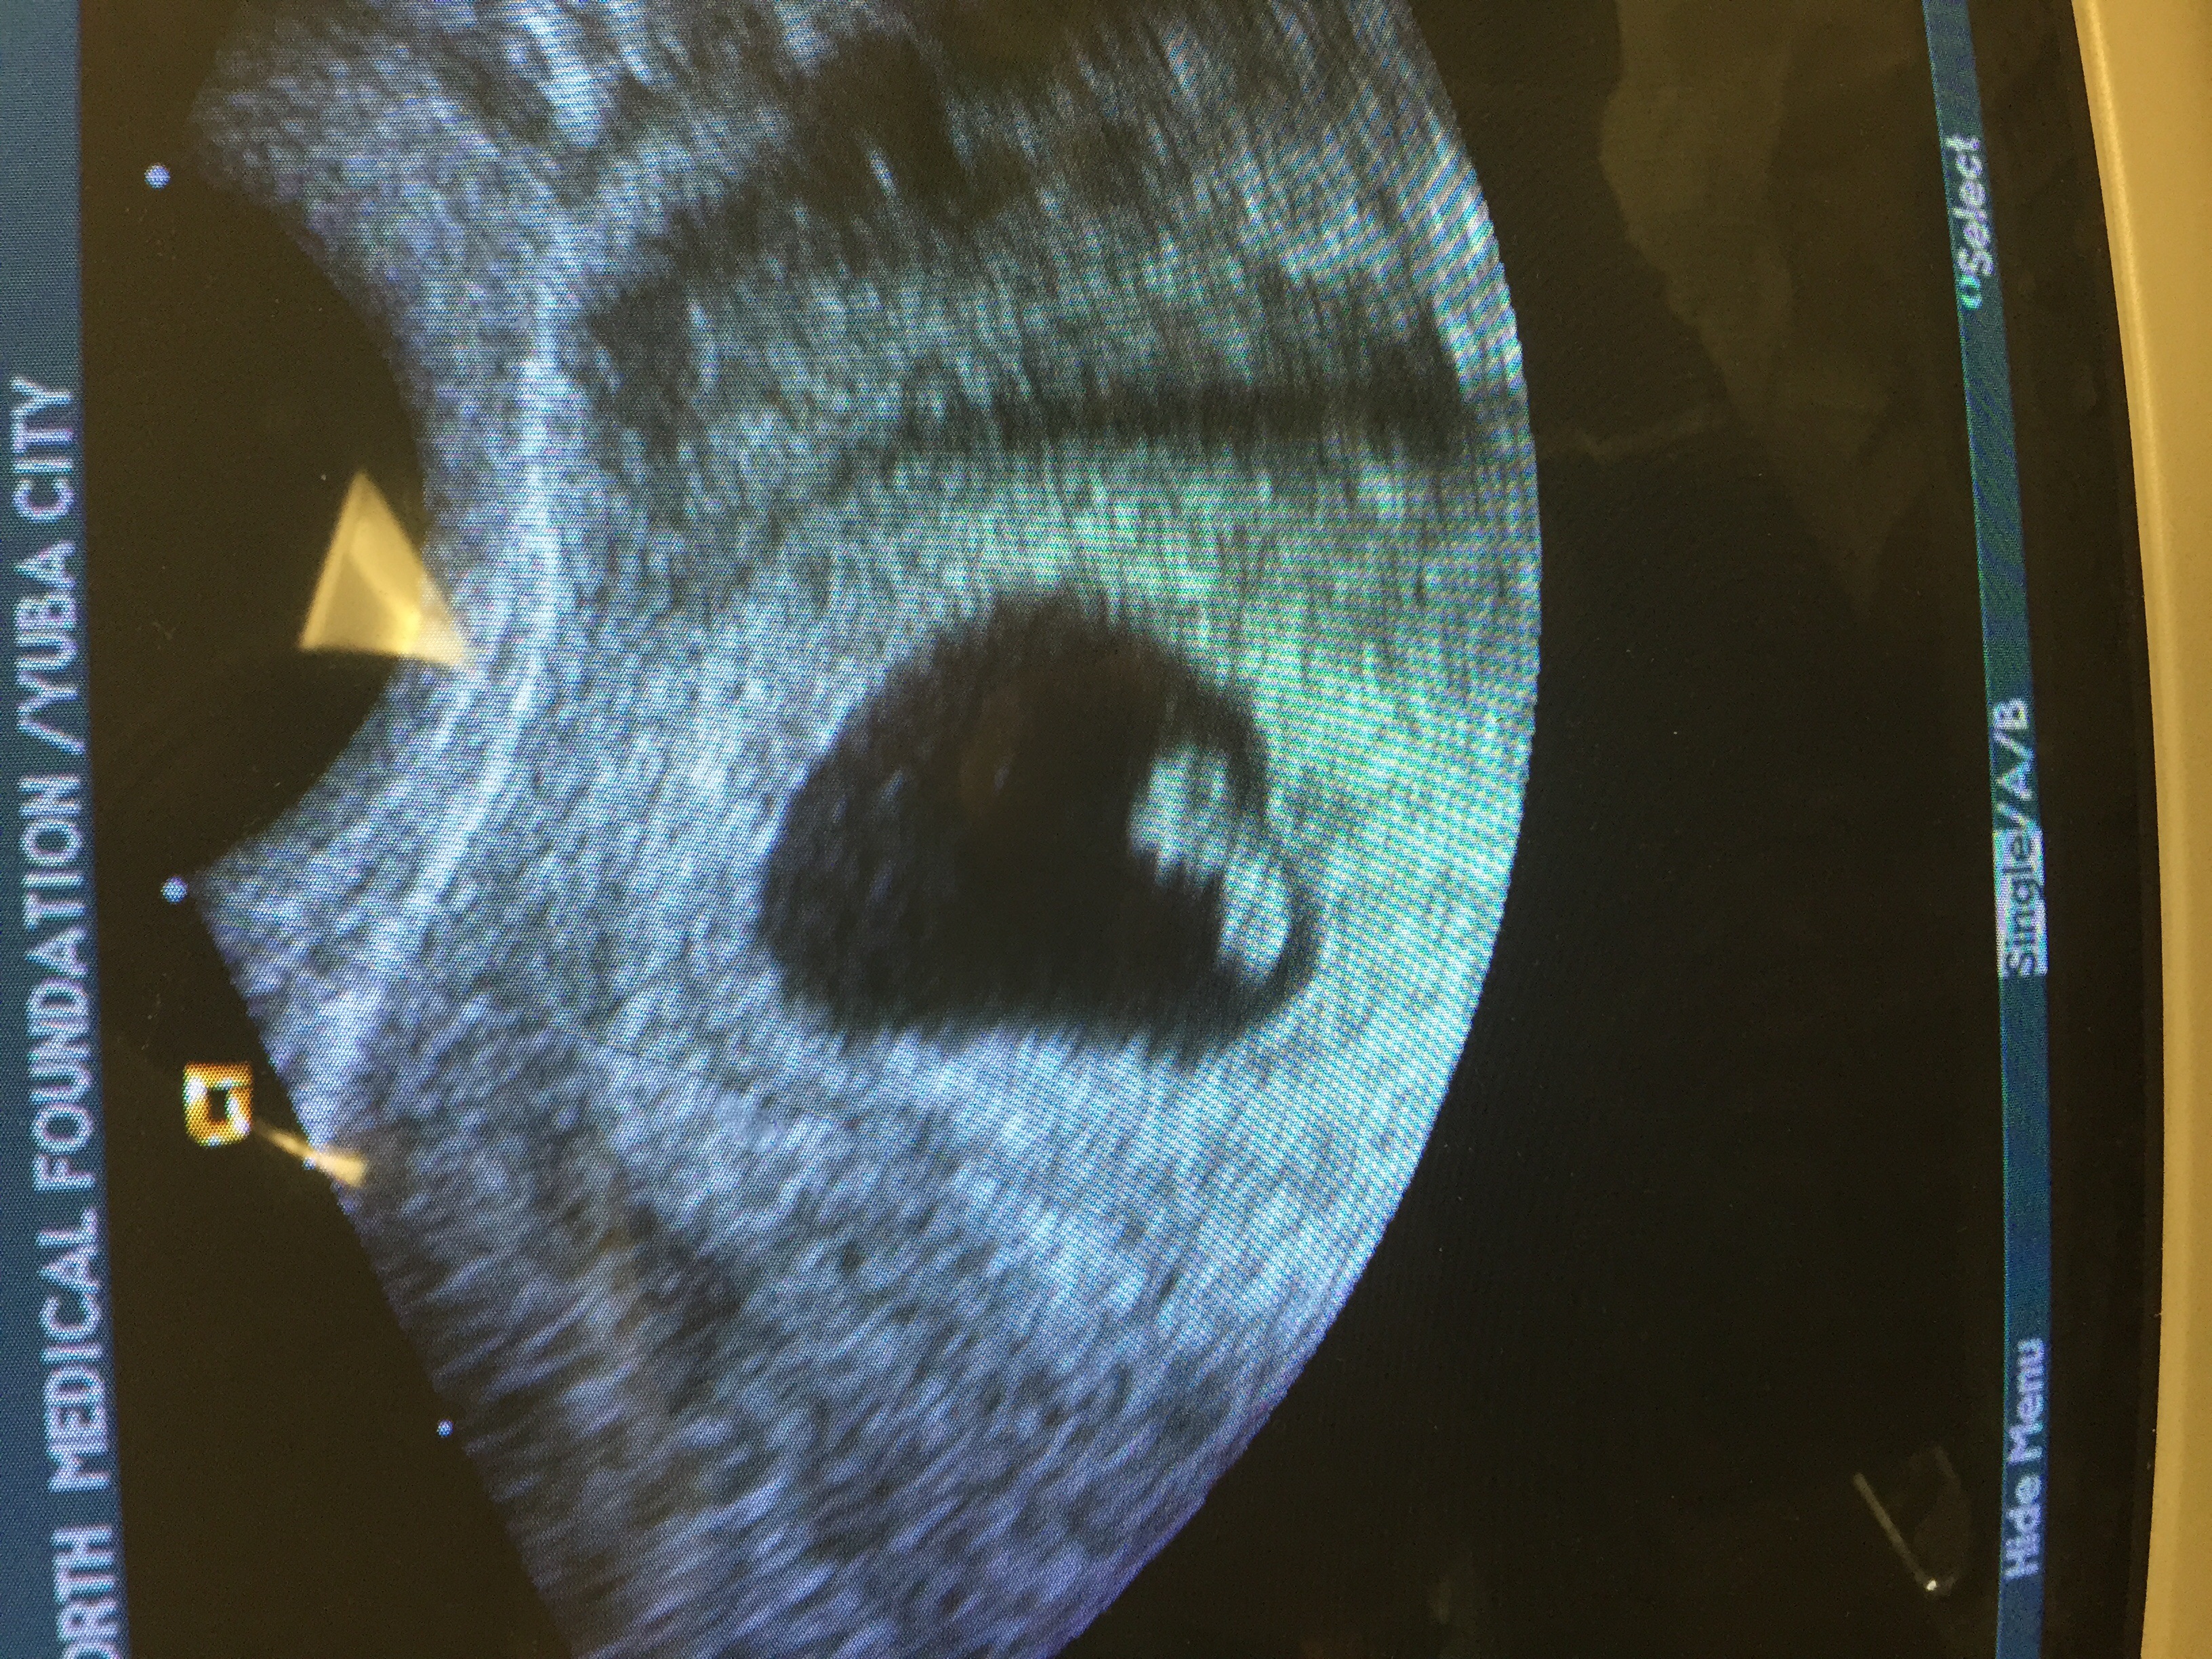

Had an unexpected US today due to some cramping. I was so expecting the worst... I am my own worst enemy but, baby has once again doubled in size from last Friday 8.21.15 to today 8.28.15!! Heartbeat today was up from 165 to 182!!!! We also got to see he/she wiggle which brought tears to my fiancées eyes... And in turn I cried. Tears of joy!! Keeping all of you in my thoughts! Positive vibes your way!